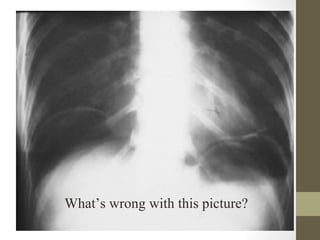

Radiographic Studies: Plain

Film

• Mostly helpful in ED for:

– Free air (suspected perforation)

– Pneumatosis (typhlitis)

– Dilated loops of bowel with air fluid levels (obstruction)

– Foreign body

• Free air seen in only 30-50% of bowel perforation

Sigmoid Volvulus

What’s wrong with this picture?

What’s wrong withthis picture?